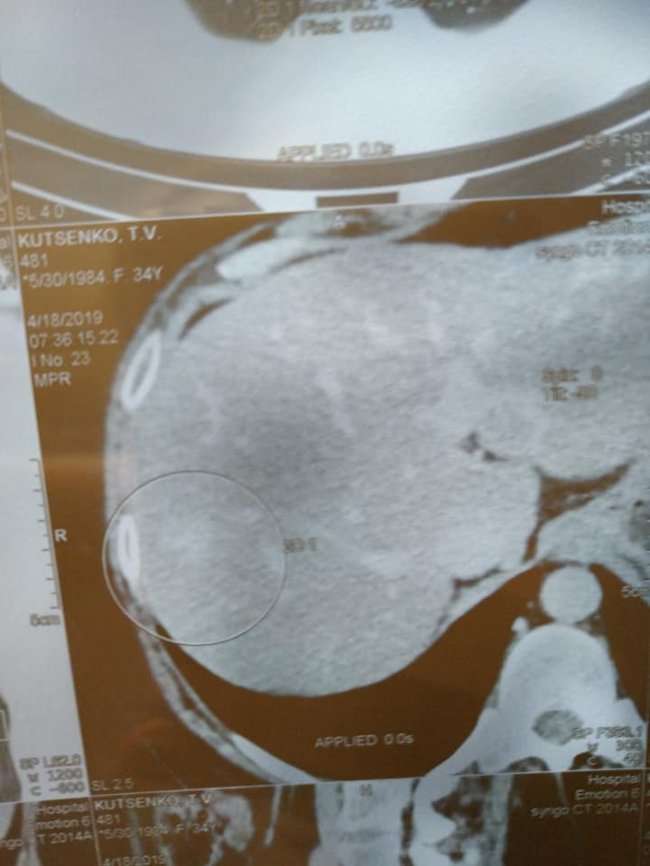

Онкохвора волинянка Тетяна Куценко розповіла про результати лікування.

Наразі метастази стають типу фібрози чи рубця, а жінка сподівається, що їх можна буде видалити. Про це вона написала на своїй сторінці у facebook.

"Слава Богу, лікування допомагає, динаміка без змін в печінці, але сама структура стала з неоднорідного однорідним, так само в легенях з ареолом матового скла.

Це означає, що метастази перетворюються в щось типу фіброзу чи рубця. Зараз я узгоджую питання про їх видалення лапараскопічне, якщо це буде можливо.

Потрібно їхати на консультацію до Києва. Тепер чекати два місяці до наступного КТ, але я вірю все-таки, що той день настане, про який я так відчайдушно мрію і метастаз не буде. Дякую, хто переживав, молився, бережи Вас усіх Боженька! ПОТРІБНА ДОПОМОГА ДЛЯ ПОВНОГО ОДУЖАННЯ!!!", - закликає Тетяна Куценко.